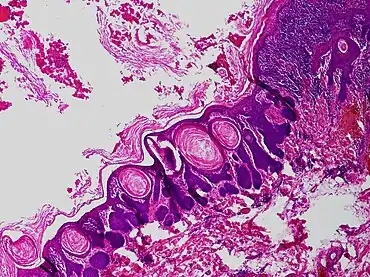

Trichofolliculoma

Trichofolliculoma is a non-cancerous, skin colored dome-shaped small or larger bump, with a central white tuft of hair typically on the face.[1] It may grow to around 7mm and sometimes there may be more than one.[1]